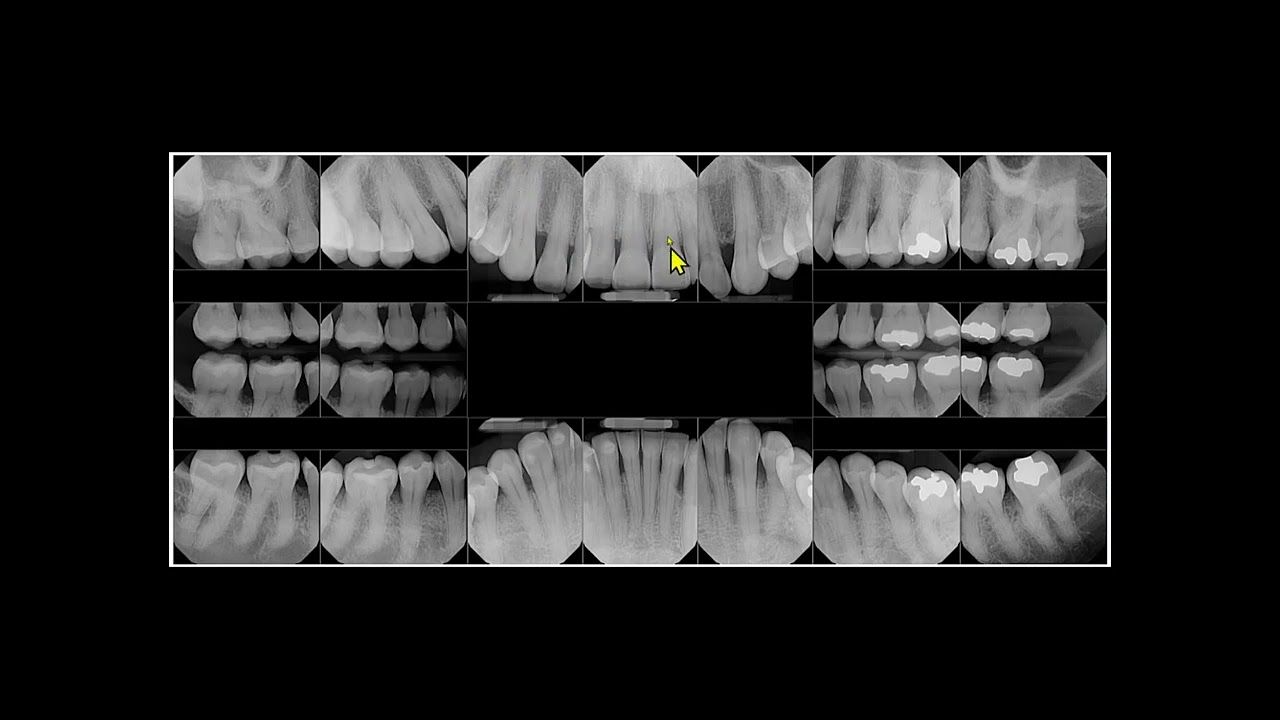

Goals of an FMX of Xrays

Jonathan Bullard